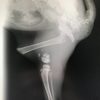

術前レントゲンです。

矢印は変位した膝蓋骨です。